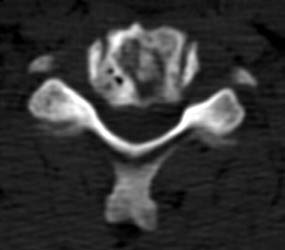

61 y.o male, s/p c4-5 discectomy and interbody fusion for myelopathy.

Initial post-operative films show bone graft intact, with mildly

prominent pervertebral soft tissues, as expected in the immediate post-operative

period. |

8 months later, the follow-up films demonstrate lucency at the

graft site worrisome for resorption. Figure _. Axial CT examination, without

contrast. |

The axial images, and the sagittal reconstructions (not

shown) show some central lucency in the region of graft placement,

suggesting partial resorption of the graft material. |